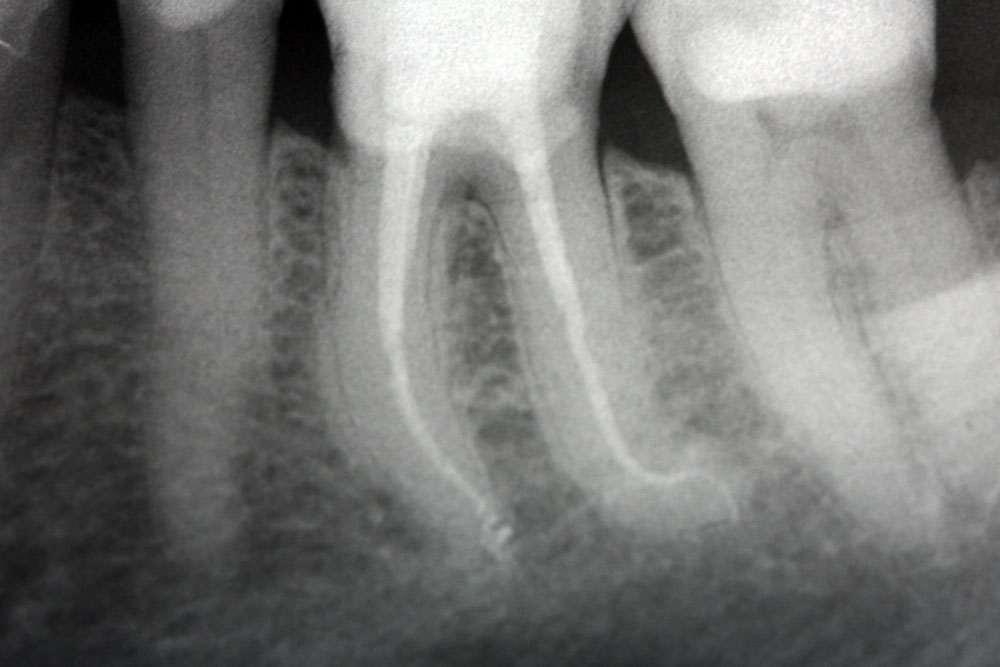

Con il termine Endodonzia si intende quella branca dell’odontoiatria che si occupa della terapia dell’endodonto, ovvero lo spazio all’interno dell’elemento dentario, che contiene la polpa dentaria, costituita da componente cellulare, vasi e nervi.

Si ricorre alla terapia endodontica qualora una lesione cariosa o traumatica al dente abbia determinato una alterazione irreversibile del tessuto pulpare, fino alla necrosi dello stesso. È possibile inoltre ricorrere a questa metodica qualora l’elemento dentario debba essere coinvolto in riabilitazioni protesiche che, a causa della notevole riduzione di tessuto dentale stesso, determinerebbero con alta probabilità un’alterazione pulpare irreversibile (necrosi pulpare per cause iatrogene).